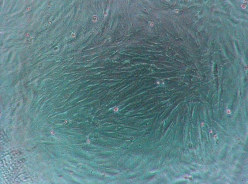

Для наглядности Доктор Фарсалинос продемонстрировал, как выглядят клетки под электронным микроскопом в разных средах: под воздействием чистого воздуха, пара от электронных сигарет и табачного сигаретного дыма.

- Клетки под воздействием табачного дыма